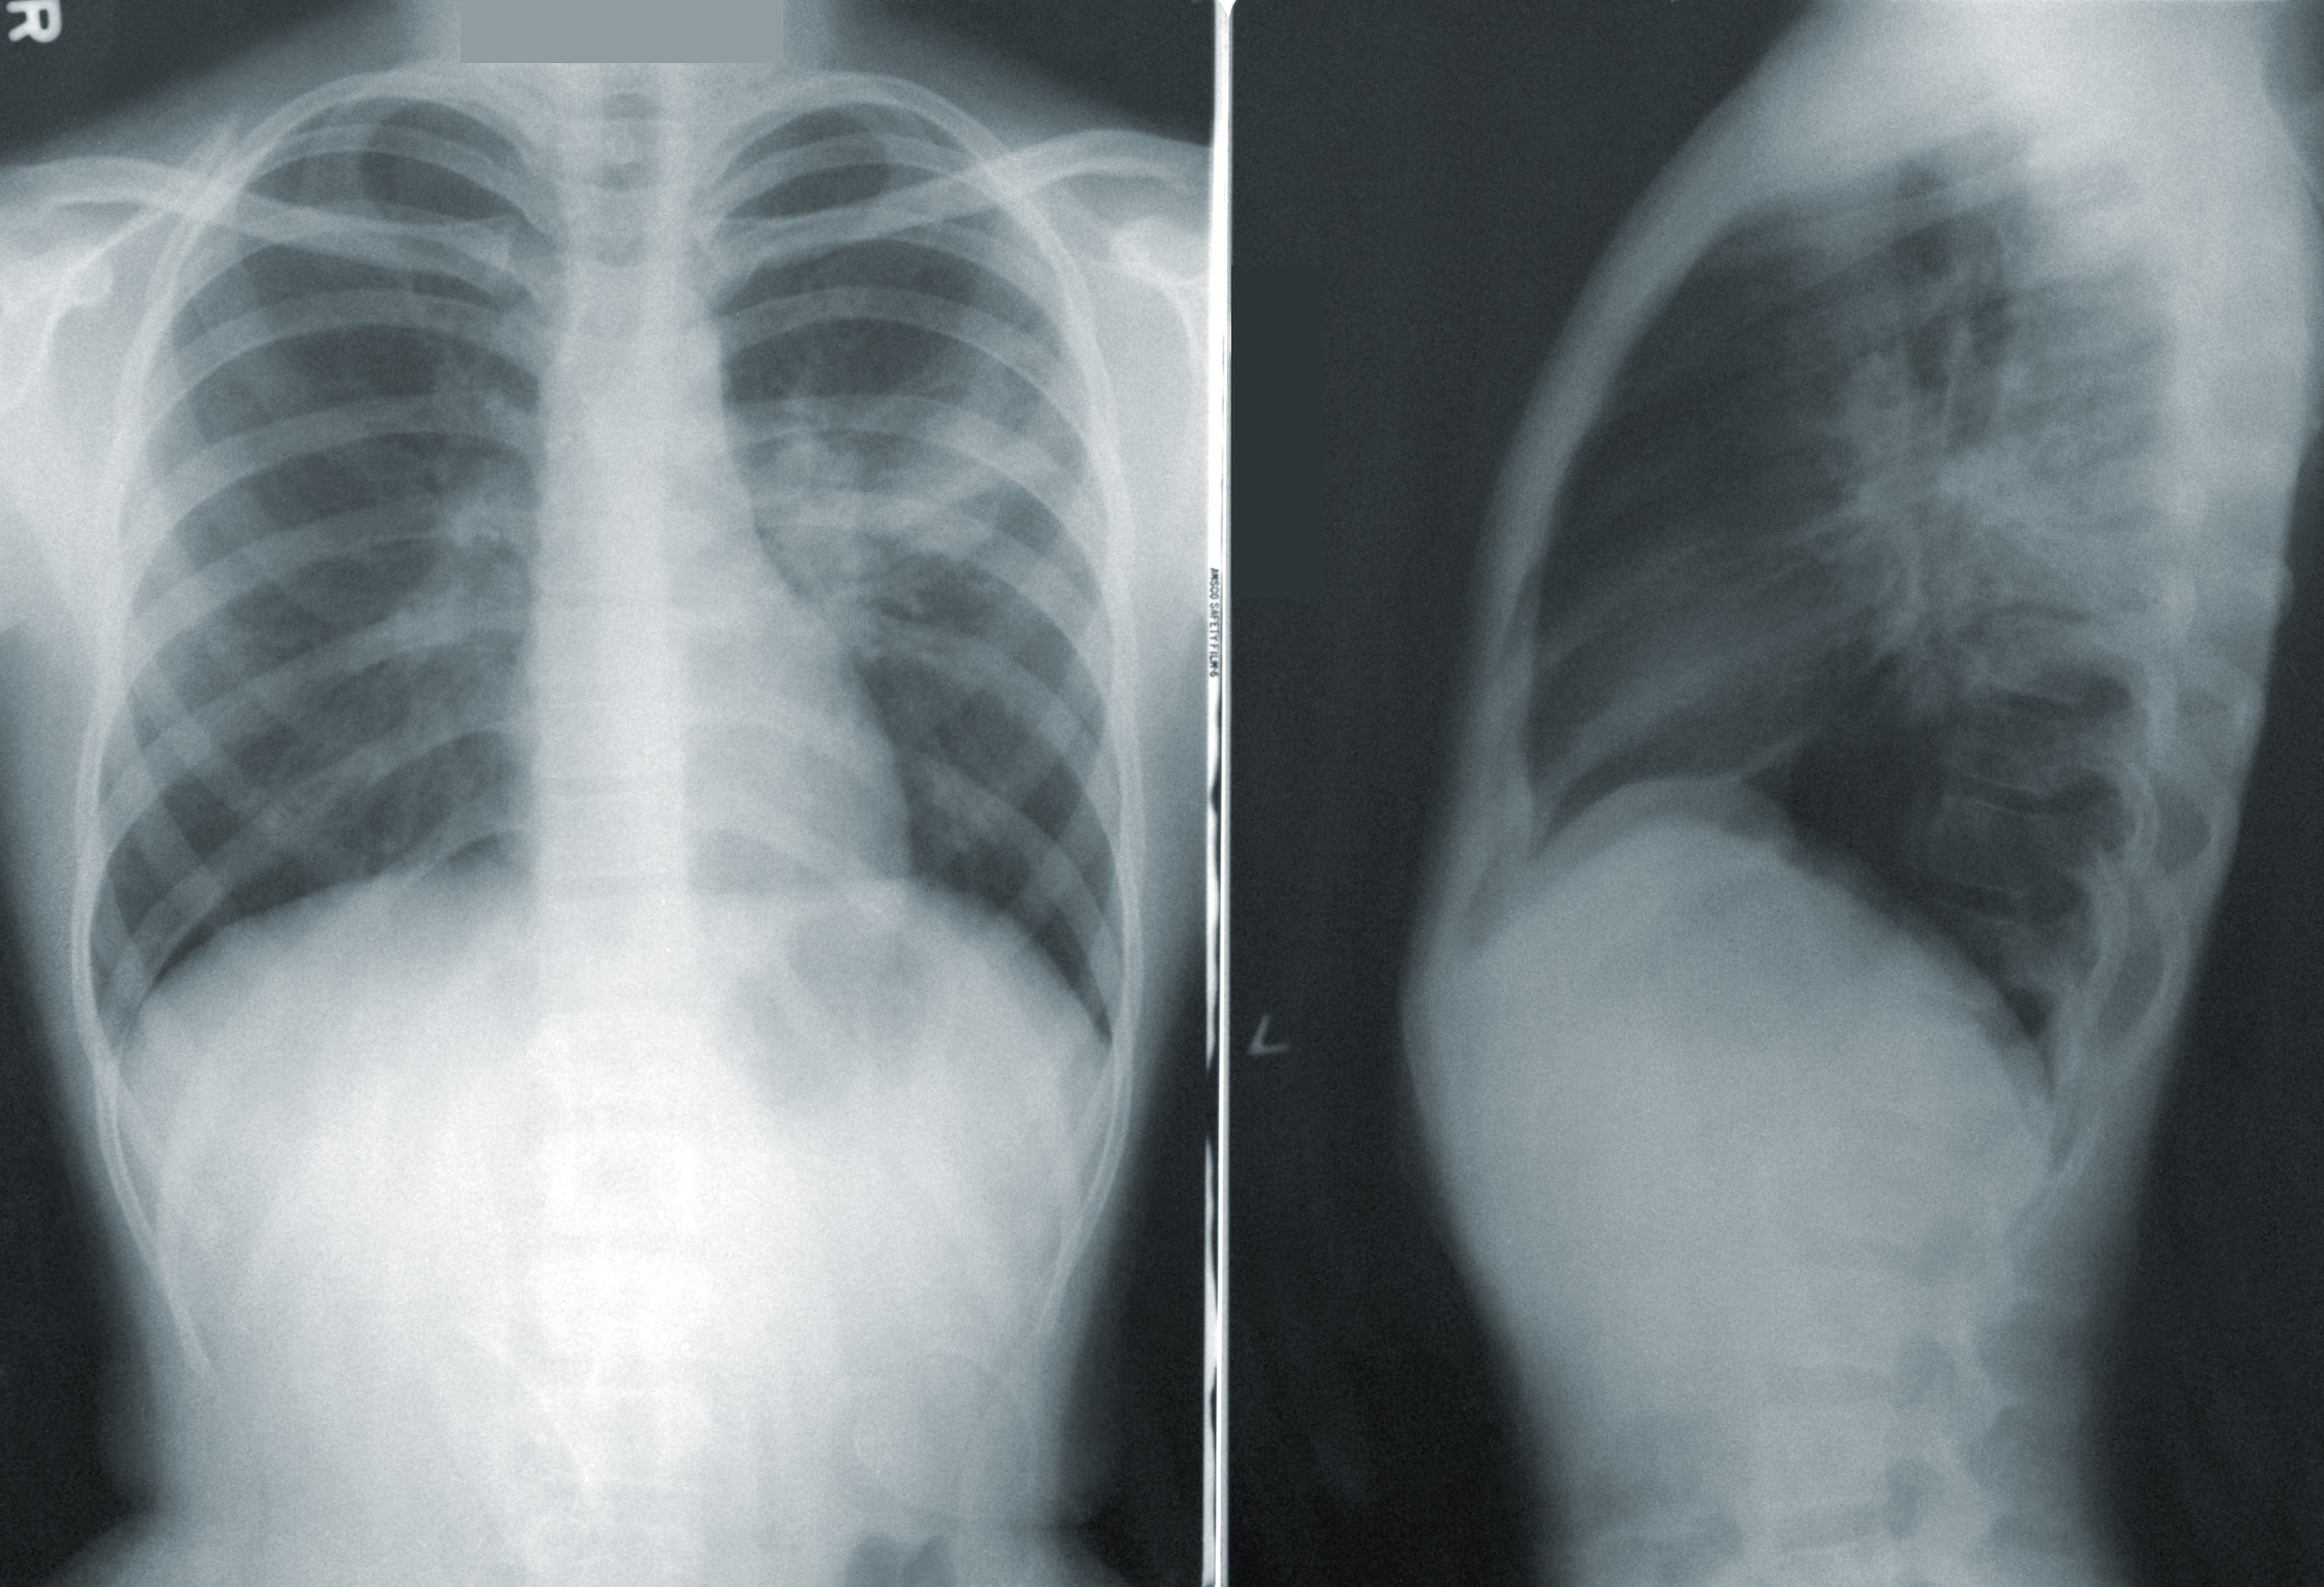

Radiology